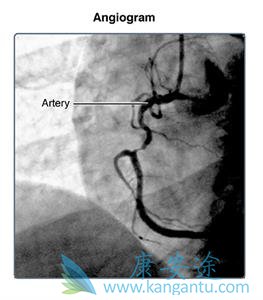

您的医生可以将导管引导到冠状动脉,并注射造影剂以检查血液通过它们。(冠状动脉是携带血液到心脏肌肉的血管)。这称为冠状动脉造影。